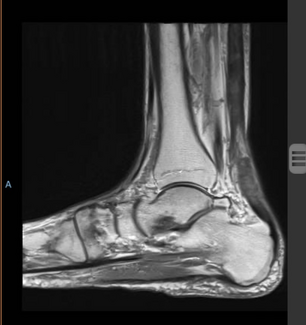

The authors describe the nonsurgical treatment of an 81-year-old man with bibasilar pneumonia who was treated with IV levofloxacin for and subsequently developed a rupture of his left Achilles tendon.